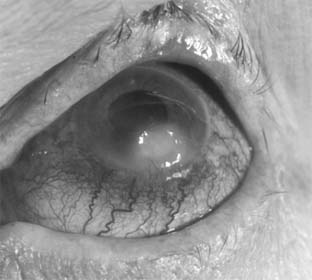

2. MOOREN'S ULCER(Figure 6-8)

The cause of Mooren's ulcer is still unknown, but an autoimmune origin is suspected. It is a marginal ulcer, unilateral in 60-80% of cases and characterized by painful, progressive excavation of the limbus and peripheral cornea that often leads to loss of the eye. It occurs most commonly in old age but does not seem to be related to any of the systemic diseases that most often afflict the aged. It is unresponsive to both antibiotics and corticosteroids. Surgical excision of the limbal conjunctiva in an effort to remove sensitizing substances has recently been advocated. Lamellar tectonic keratoplasty has been used with success in selected cases. Systemic immunosuppressive therapy may be helpful in advanced disease.

Figure 6-8

Figure 6-8: Advanced Mooren's ulcer.